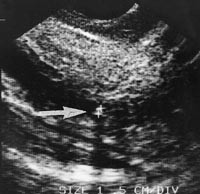

Vi behandlet 21 av de 29 pasientene med påvist gallegangskonkrement med postoperativ ERC. De resterende åtte pasientene ble observert på grunn av små steiner (< 5 mm) (fig 5). Fire av disse er senere behandlet med ERC og steinekstraksjon, mens de øvrige fortsatt er symptomfrie. Hos e…n pasient var undersøkelsen falskt negativ. Dette var en overvektig pasient hvor prosedyren var teknisk meget vanskelig. Den intrapankreatiske del av gallegangen kunne ikke visualiseres optimalt, og dermed ble sannsynligvis et lite preampullært konkrement oversett.

Laparoskopisk ultralyd er en god undersøkelsesmetode for påvisning av choledochuskonkrementer. Ved god undersøkelsesteknikk kan konkrementer< 5 mm lett identfiseres. Størrelsen av konkrementer som avgår gjennom papillen spontant kjennes ikke. Teoretisk kan man si at de minste konkrementer har lettere for å passere. Selv om våre tall er små og inkonklusive, passerte 50 % av konkrementene< 5 mm komplikasjonsfritt. Man kan anta at små konkrementer påvist ved laparoskopisk ultralyd sannsynligvis vil passere spontant uten ytterligere behandling. Pasienter som har gjennomgått gallesteinsassosiert pankreatitt må få sanert gallegangene uavhengig av konkrementets størrelse.